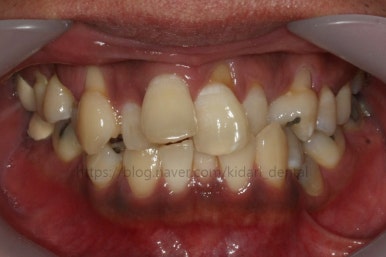

부산치아교정 키다리아저씨치과에 처음 내원 당시의 입안 모습입니다.

여러 가지 문제점이 있는데 하나씩 살펴볼게요.

치열이 많이 삐뚤하네요.

많이 삐뚠 상태에서 장기간 사용하다 보면 안좋은 방향으로 치아가 힘을 받게 되고 마모나 치아 목부분 패임이 심해집니다.

양치가 힘들어요. 양치가 힘들다 보니 세게 닦게 되고 치아 손상은 더 심해져요. 25세의 나이였는데 나이에 비해서 치아나이가 굉장히 많은거죠.